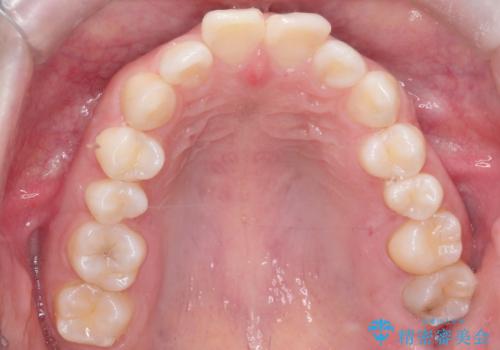

- 前歯のデコボコ(叢生)を気にされてご来院されました。精密な検査の結果、歯が並ぶスペースが不足していることが判明。患者様のご希望から、透明で目立ちにくいインビザライン(マウスピース矯正)による治療計画を立案しました。抜歯を避け、奥歯全体を奥へ動かす遠心移動という方法でスペースを確保し、前歯の叢生を解消することを目指します。

今回の矯正治療では、透明なマウスピース型の装置インビザラインを使用しました。この装置は取り外し可能で、日常生活で目立ちません。治療は、緻密に計算された計画に基づき、段階的に作製されたマウスピースを交換していくことで、奥歯から順に全体を後方へ移動させる遠心移動を実施。これにより、前歯を並べるための十分なスペースが確保され、デコボコが解消されました。抜歯することなく、機能的にも審美的にも整った美しい歯並びを獲得していただけました。